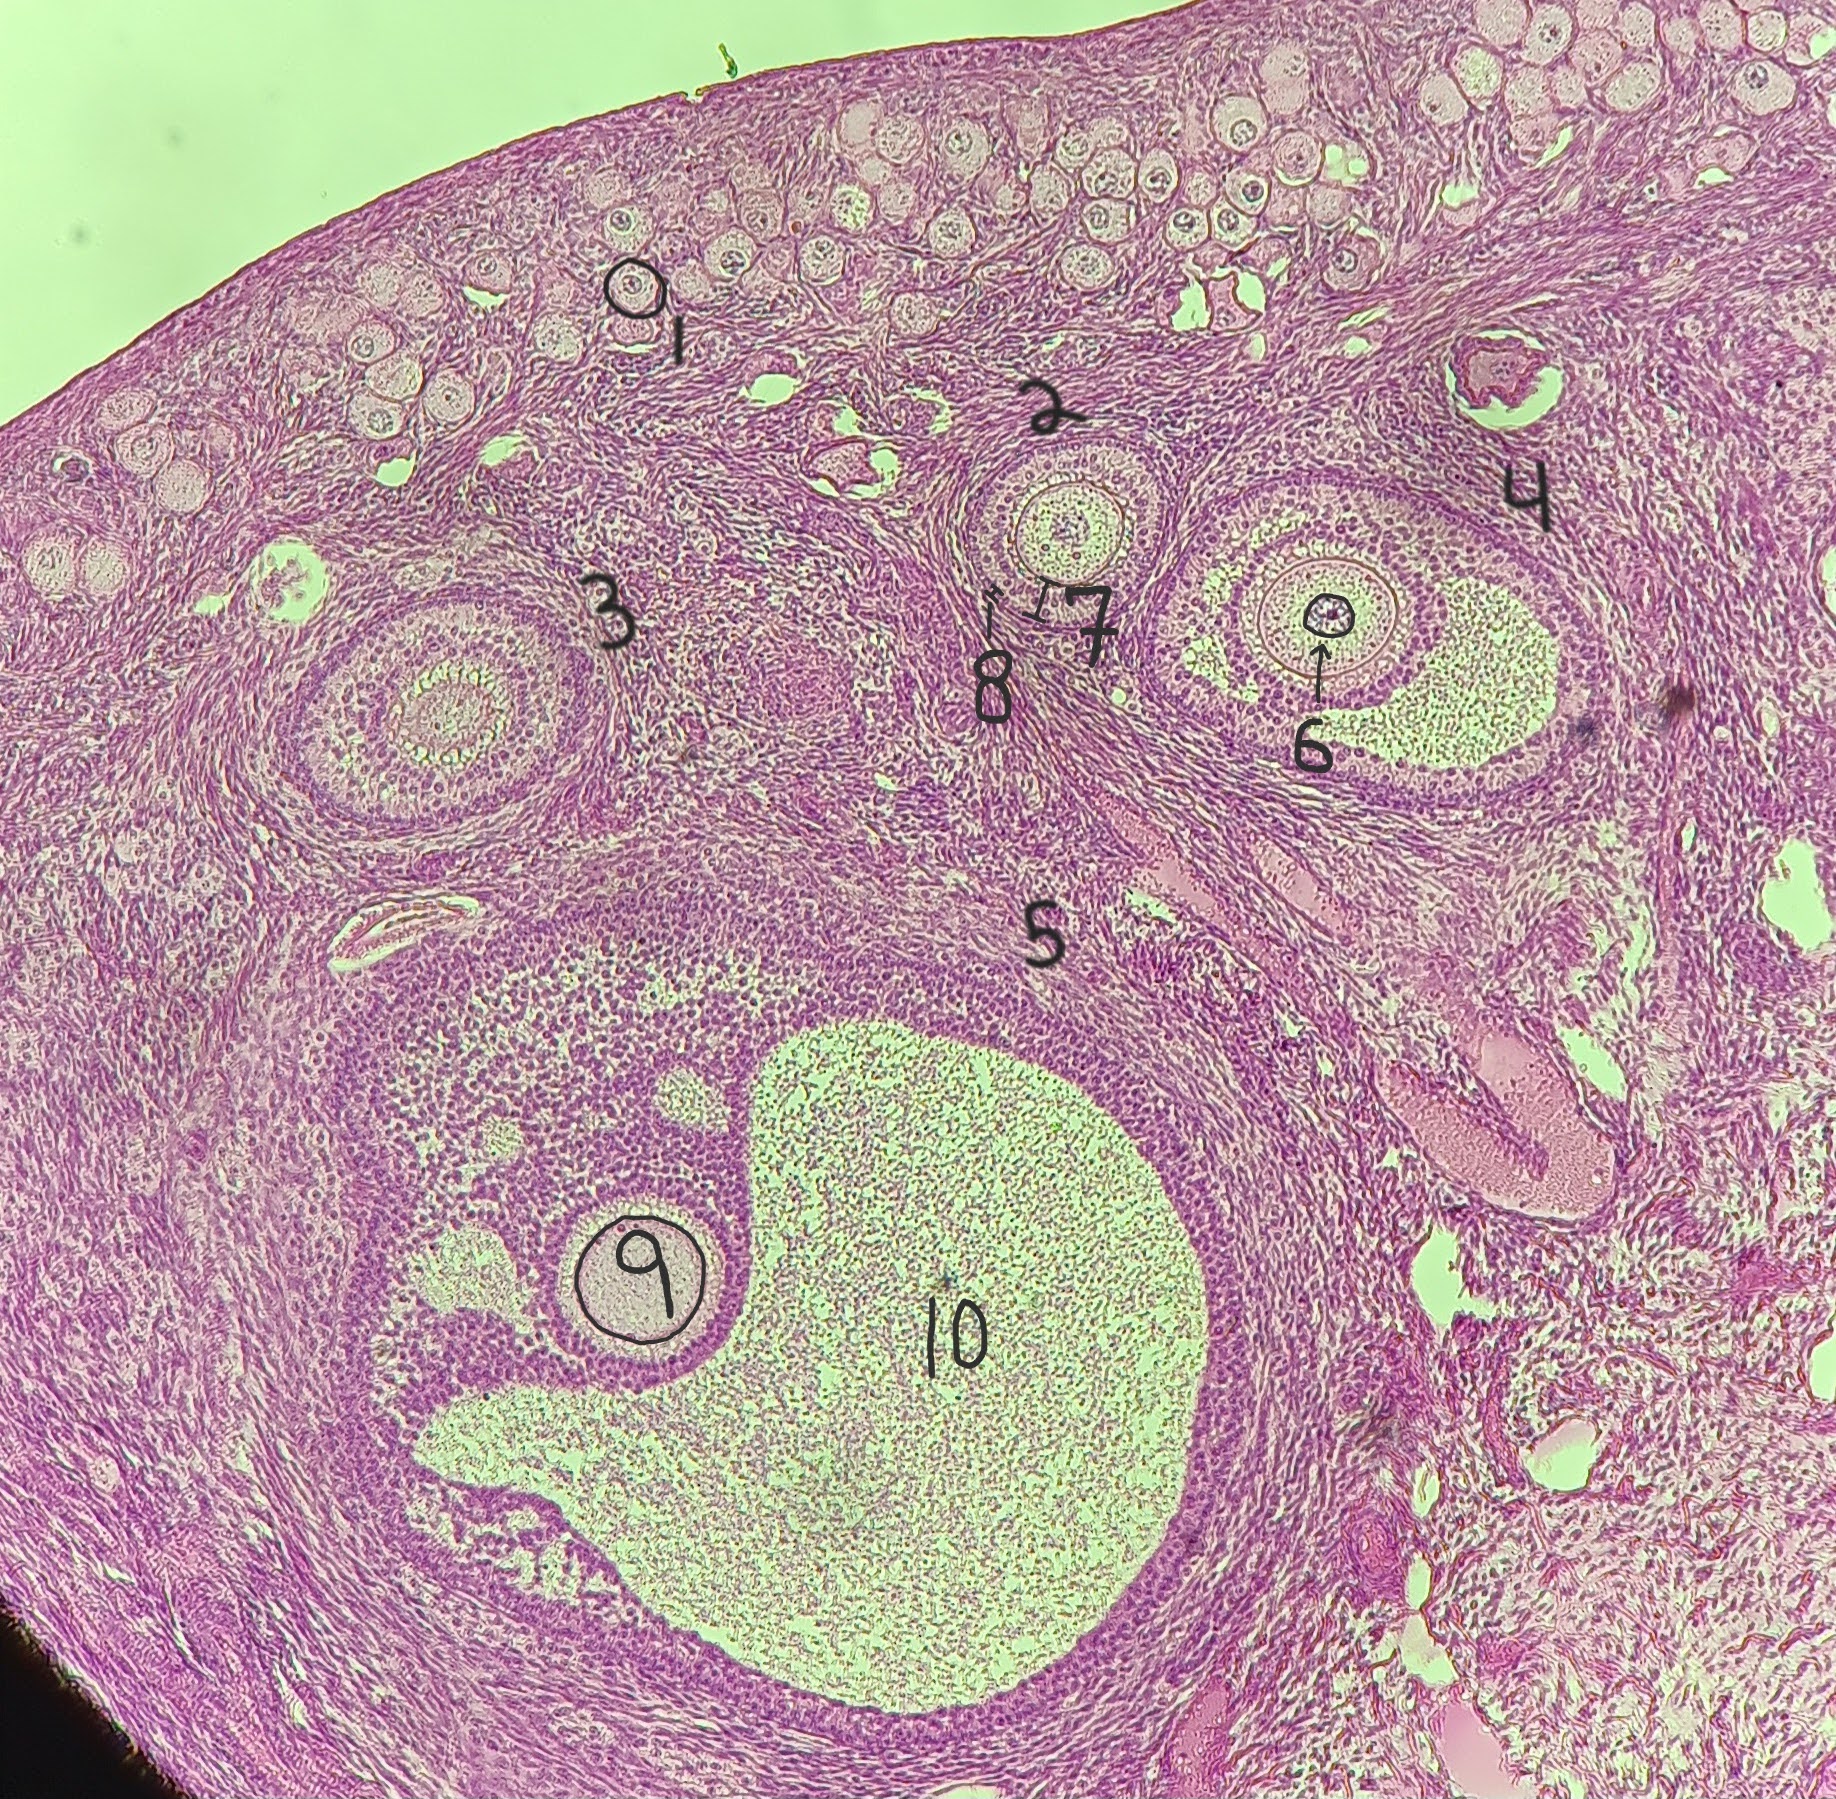

Primordial follicle

1

Primordial follicle

1

Primary follicle

2

2

Secondary follicle

3

3

Tertiary follicle

4

4

Mature follicle

5

Mature follicle

7

Antrum

10

Zona pellucida

9

Theca folliculi

8

corpus luteum

8

early corpus luteum

9

late corpus luteum

10